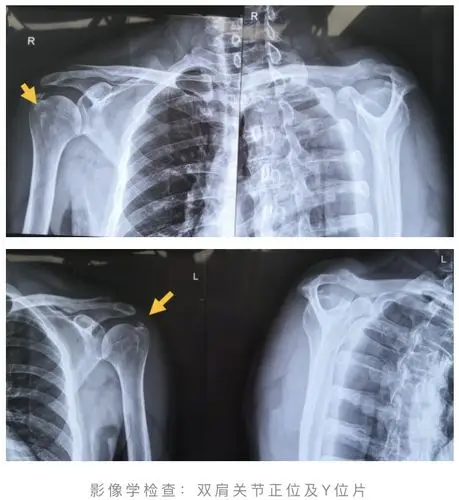

肌腱炎|钙化灶|肩关节_新浪新闻